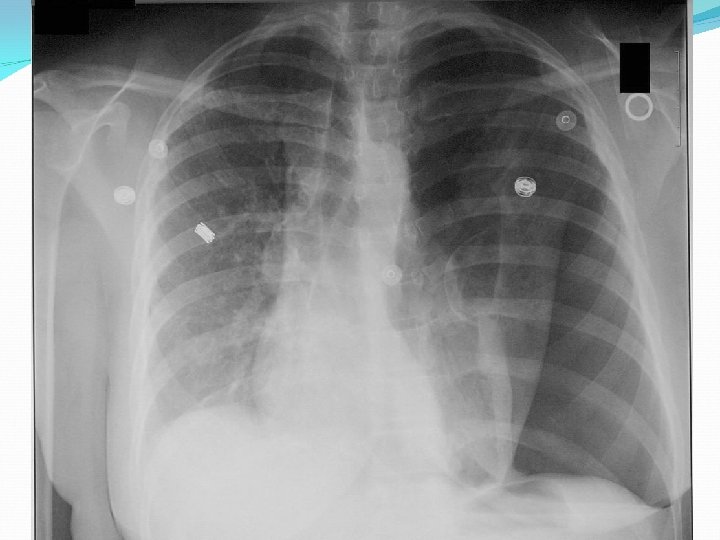

Central venous catheter - What to do after cannulation sterile cover control chest X-ray exclude PNO check position of catheter

Central venous catheter - Complications arythmias PNO bleeding punction of arteria damage of plexus brachialis air emboly thrombosis (v. femoralis) infection, sepsis